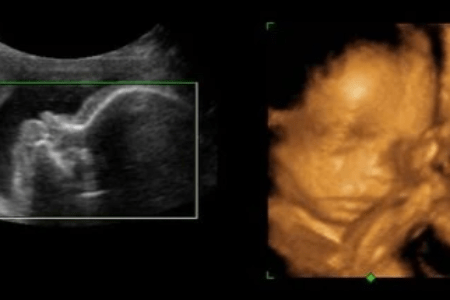

Le dépistage in utéro